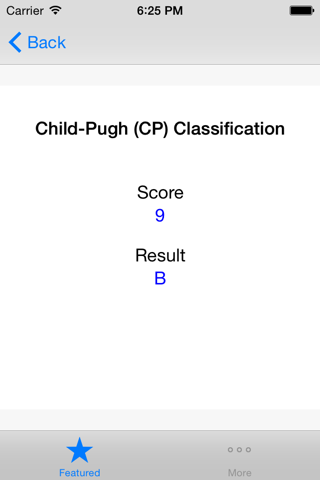

Child-Pugh (CP) Classification

Child-Pugh (CP) classification was originally designed to determine the risk of portocaval shunt surgery in cirrhotic patients. CP classification provides mortality risk with abdominal surgery, survival rates and a likelihood of developing complications secondary to underlying cirrhosis. The input variables include serum bilirubin, serum albumin, presence of ascites or encephalopathy and prothrombin time. The minimum CP score is 5 whereas the maximum possible score is 15. A score of 5-6 is classified as class A indicating well compensated cirrhosis, whereas a score of 7-9 is class B with significant functional compromise, and a score of 10-15 is a class C with decompensated cirrhosis. This application implements the CP classification system and assigns a score and stage based on the user provided input.